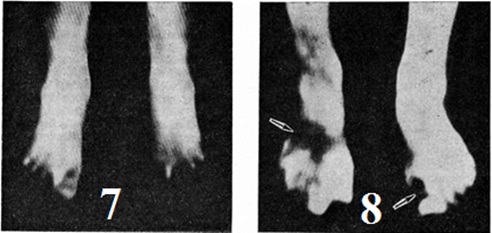

Рис. 3.

Вид стоп при отморожении IV степени: а — мумификация I и II пальцев с начальными явлениями отторжения (сухая гангрена); б — ткани I—III пальцев и дистальный отдел стопы расплавлены, стопа резко отёчна (влажная гангрена).

Клиническая картина. Основными симптомами Отморожение в дореактивном периоде являются побеление кожи в зоне охлаждения (цветной рисунок 7) и потеря чувствительности в охлаждённых тканях. При Отморожение, возникшем во влажной среде (промокшая обувь), нередко отмечаются синюшность и покраснение кожи поражённых конечностей (а именно они чаще всего поражаются), усиливающиеся после согревания. Пострадавшие жалуются на тяжесть в конечностях, потерю чувства опоры, невозможность самостоятельно ходить. Общее состояние больных при Отморожение конечностей может сохраняться неизменённым, однако в случаях, когда Отморожение сопровождается значительным общим охлаждением тела, могут наблюдаться признаки охлаждения организма (смотри полный свод знаний) — состояние депрессии, нарушение дыхания, одышка, тахикардия. При тяжёлых Отморожение возможно падение АД и развитие шока (смотри полный свод знаний).

Клиническая картина Отморожение в реактивном периоде проявляется серозным или серозно-геморрагическим воспалением (холодовый дерматит) с исходом в асептический некроз. Наиболее ранними признаками реактивного периода являются развитие отёка, покраснение (с синюшным оттенком) кожи (цветной рисунок 8), затем (кроме отморожения I степени) появление пузырей. Геморрагическое содержимое пузырей чаще всего свидетельствует о том, что тяжесть Отморожение превышает вторую степень. Уже в первые минуты согревания, ещё до развития видимых воспалительных и деструктивных изменений, возникает боль, интенсивность и длительность которой зависит от тяжести поражения.

Рис. 7. Вид стоп при отморожении в дореактивном периоде, кожа в местах поражения побелевшая.

Рис. 8. Стопа при отморожении после согревания, виден отёк.